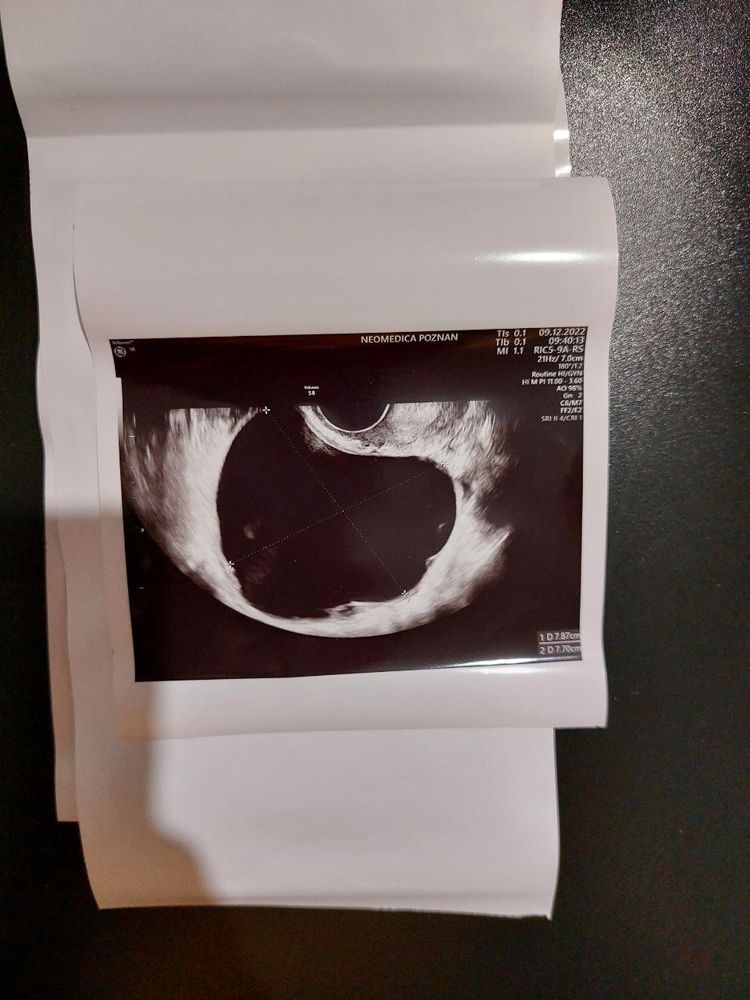

Фолликулярная киста. Прошла сама после М Изображение